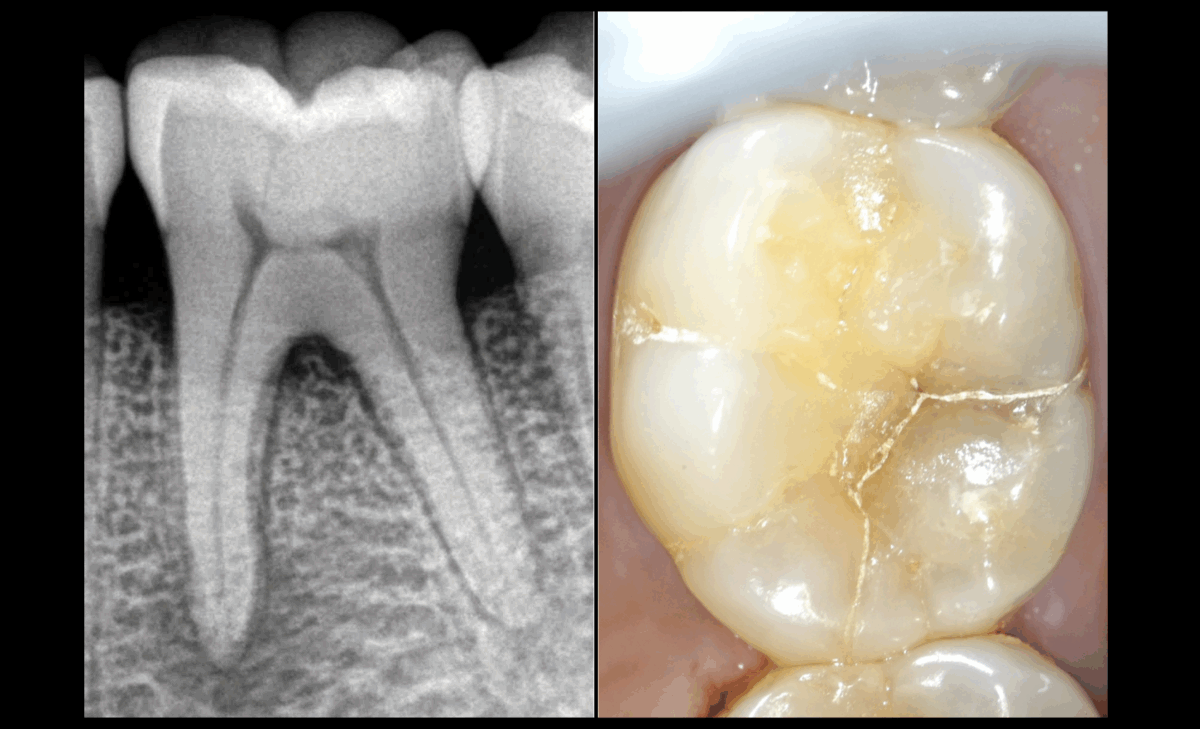

🦷 Nécrose pulpaire

😖 Parodontite apicale symptomatique

📉 Alvéolyse horizontale

⚡ Fêlure

🛠️ 𝐏𝐥𝐚𝐧 𝐝𝐞 𝐭𝐫𝐚𝐢𝐭𝐞𝐦𝐞𝐧𝐭

🔹 Traitement canalaire / mise en sous-occlusion (protection biomécanique)

🔹 Recouvrement cuspidien (overlay) – Dr A. Sarfati

🔹 Traitement parodontal – Dr A. Sarfati

❓ 𝐉𝐮𝐬𝐪𝐮’𝐨𝐮̀ 𝐚 𝐞́𝐭𝐞́ 𝐭𝐫𝐚𝐯𝐚𝐢𝐥𝐥𝐞́𝐞 𝐥𝐚 𝐟𝐞̂𝐥𝐮𝐫𝐞 𝐝𝐚𝐧𝐬 𝐜𝐞 𝐜𝐚𝐬 ?

➡️ Jusqu’aux limites du champ opératoire.